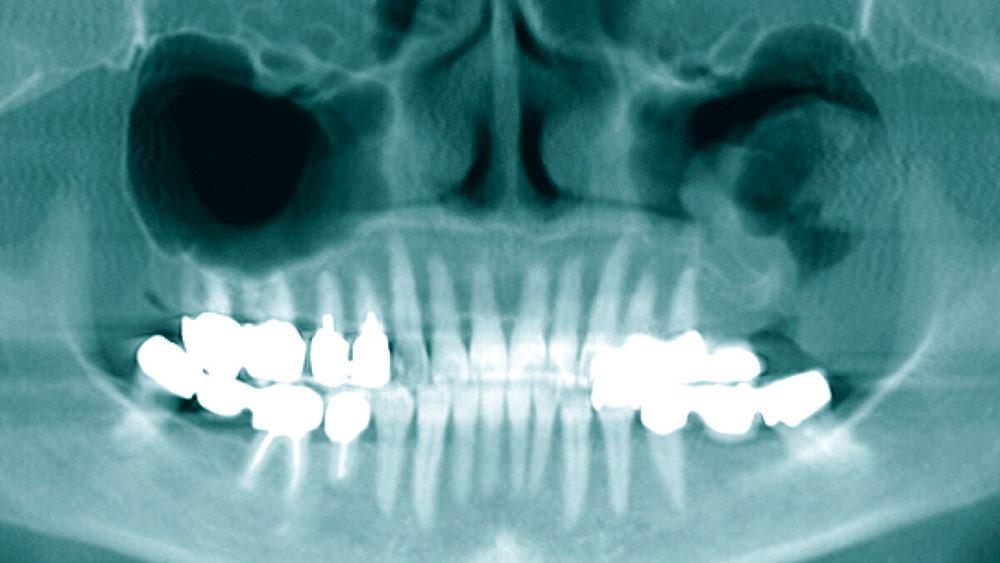

Die präoperativ durchgeführte Digitale Volumentomografie (DVT) zeigte eine zystische Raumforderung, die fast zwei Drittel der linken Kieferhöhle einnahm. Die Raumforderung hatte randständig eine weichgewebedichte Opazität mit zentraler Transluzenz und erschien fast „seifenblasenartig“. In regio 26/27 zeigte sich die bereits klinisch auffällige MAV. Radiologisch befand sich der Zahn 25 in direkter Nähe zum Befund. Das restliche Gebiss wies neben konservierenden und prothetischen Maßnahmen keine weiteren Auffälligkeiten auf (Abbildung 1).